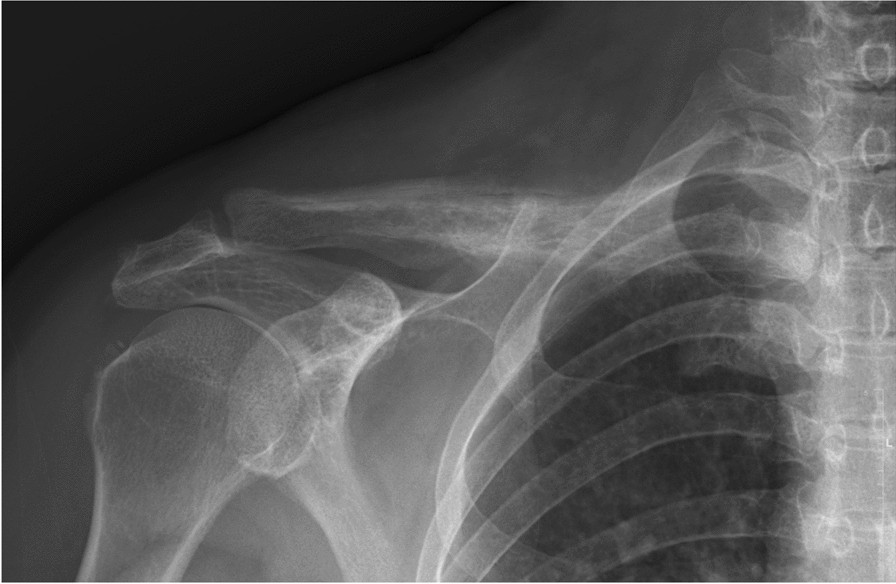

Fig. 1From: A rare case report: an inextricable shoulder pain as the exclusive presentation of lung adenocarcinoma with metastasis over contralateral claviclePlain radiograph of the right clavicle showed osteolytic moth-eaten appearance with osteosclerotic periosteal reactionBack to article page